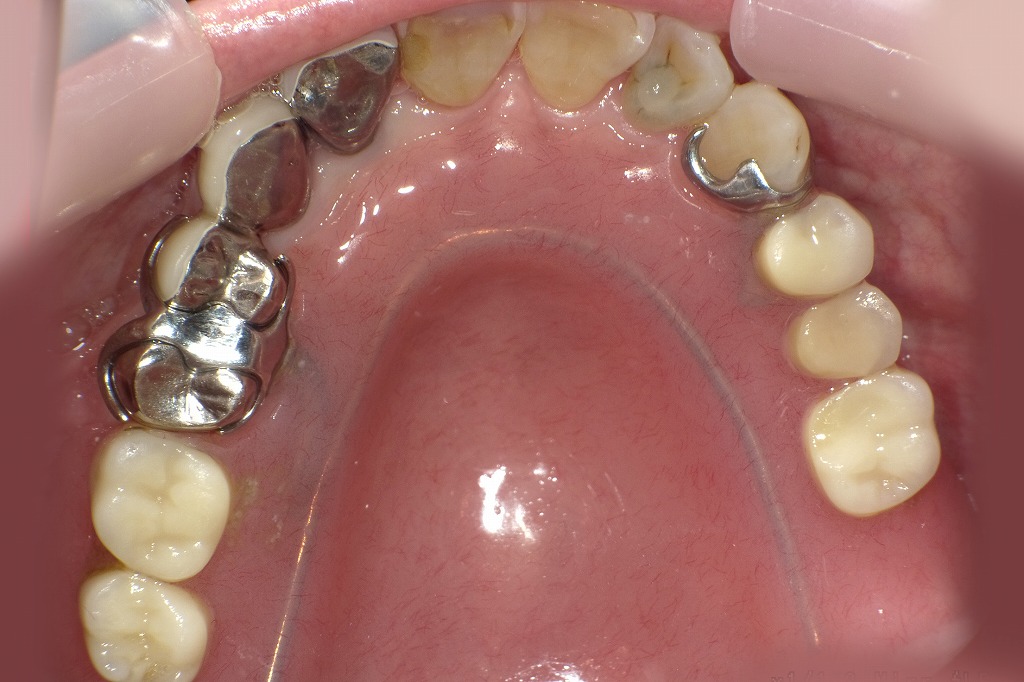

🦷 保険適用で作れる部分入れ歯の具体例(上顎・下顎のパターン)

部分入れ歯の形は、欠損している歯の位置と本数に応じて設計が変わります。以下はよくある例です。

上顎の例:

- 両側奥歯がない場合:U字型や馬蹄形のデザイン

- 前歯と小臼歯を残して奥歯を補うタイプ:前歯や小臼歯にクラスプがかかる設計

下顎の例:

- 前歯と小臼歯、第一大臼歯が残っていて奥歯を補う場合:バー(連結部)が舌の下に通る構造

- 左右非対称な欠損では、片側に大きく広がる設計

どちらも基本的にはレジン床(プラスチックのベース)に人工歯と金属クラスプが付属しており、装着時に違和感が出ることもあります。